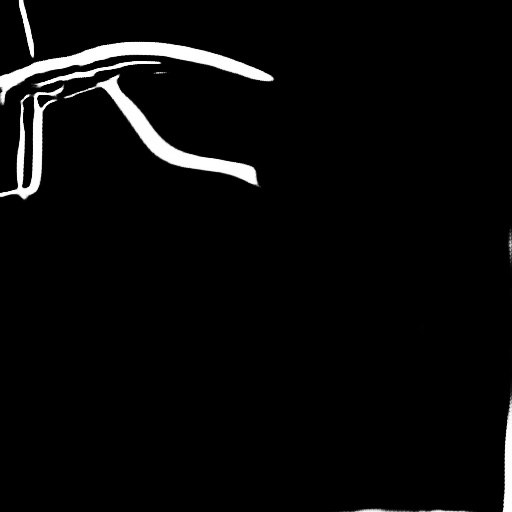

4.1 XACV Dataset

We collect 111 complete records of coronary artery X-ray videos, encompassing the injection, flow through the blood vessels around the heart, and dissipation of the contrast agent. Subsequently, we establish the XACV (X-ray Angiography Coronary Video) dataset. Each video consists of varying numbers of high-resolution coronary artery X-ray images. We invite experienced radiologists to annotate the vascular regions, focusing on one or two frames where the contrast agent is most prominent in each video. The XCAD dataset contains only a single image, and the CADICA video dataset does not provide corresponding ground truth. Therefore, in the following experiments, we conduct all the analyses on our collected XACV dataset and the corresponding GT for each sequence. In Figure 5, we show that compared to other publicly available datasets, XCAD [33] and CADICA [19], our dataset exhibits finer annotations in the vascular regions, providing an advantage for future related tasks. The development and use of our dataset have been approved by our institution’s IRB.